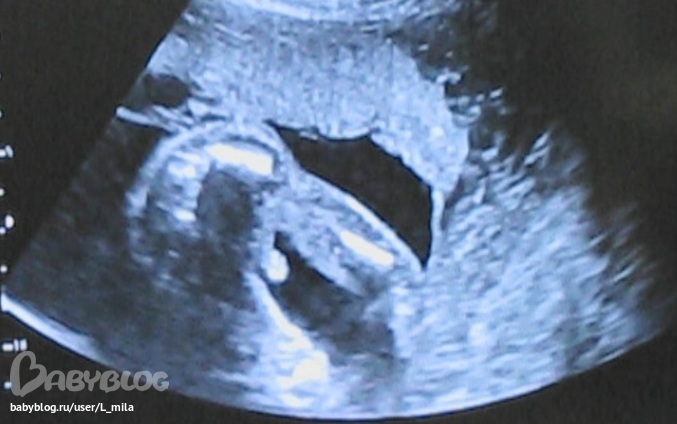

да:) у нас еще есть фото,где видно прям яички и писю:) но не ясно,что там ноги:)вот и выложила эту:)

Кайф!.. У нас тоже почти такой же снимок с писюном ;))

мужики!